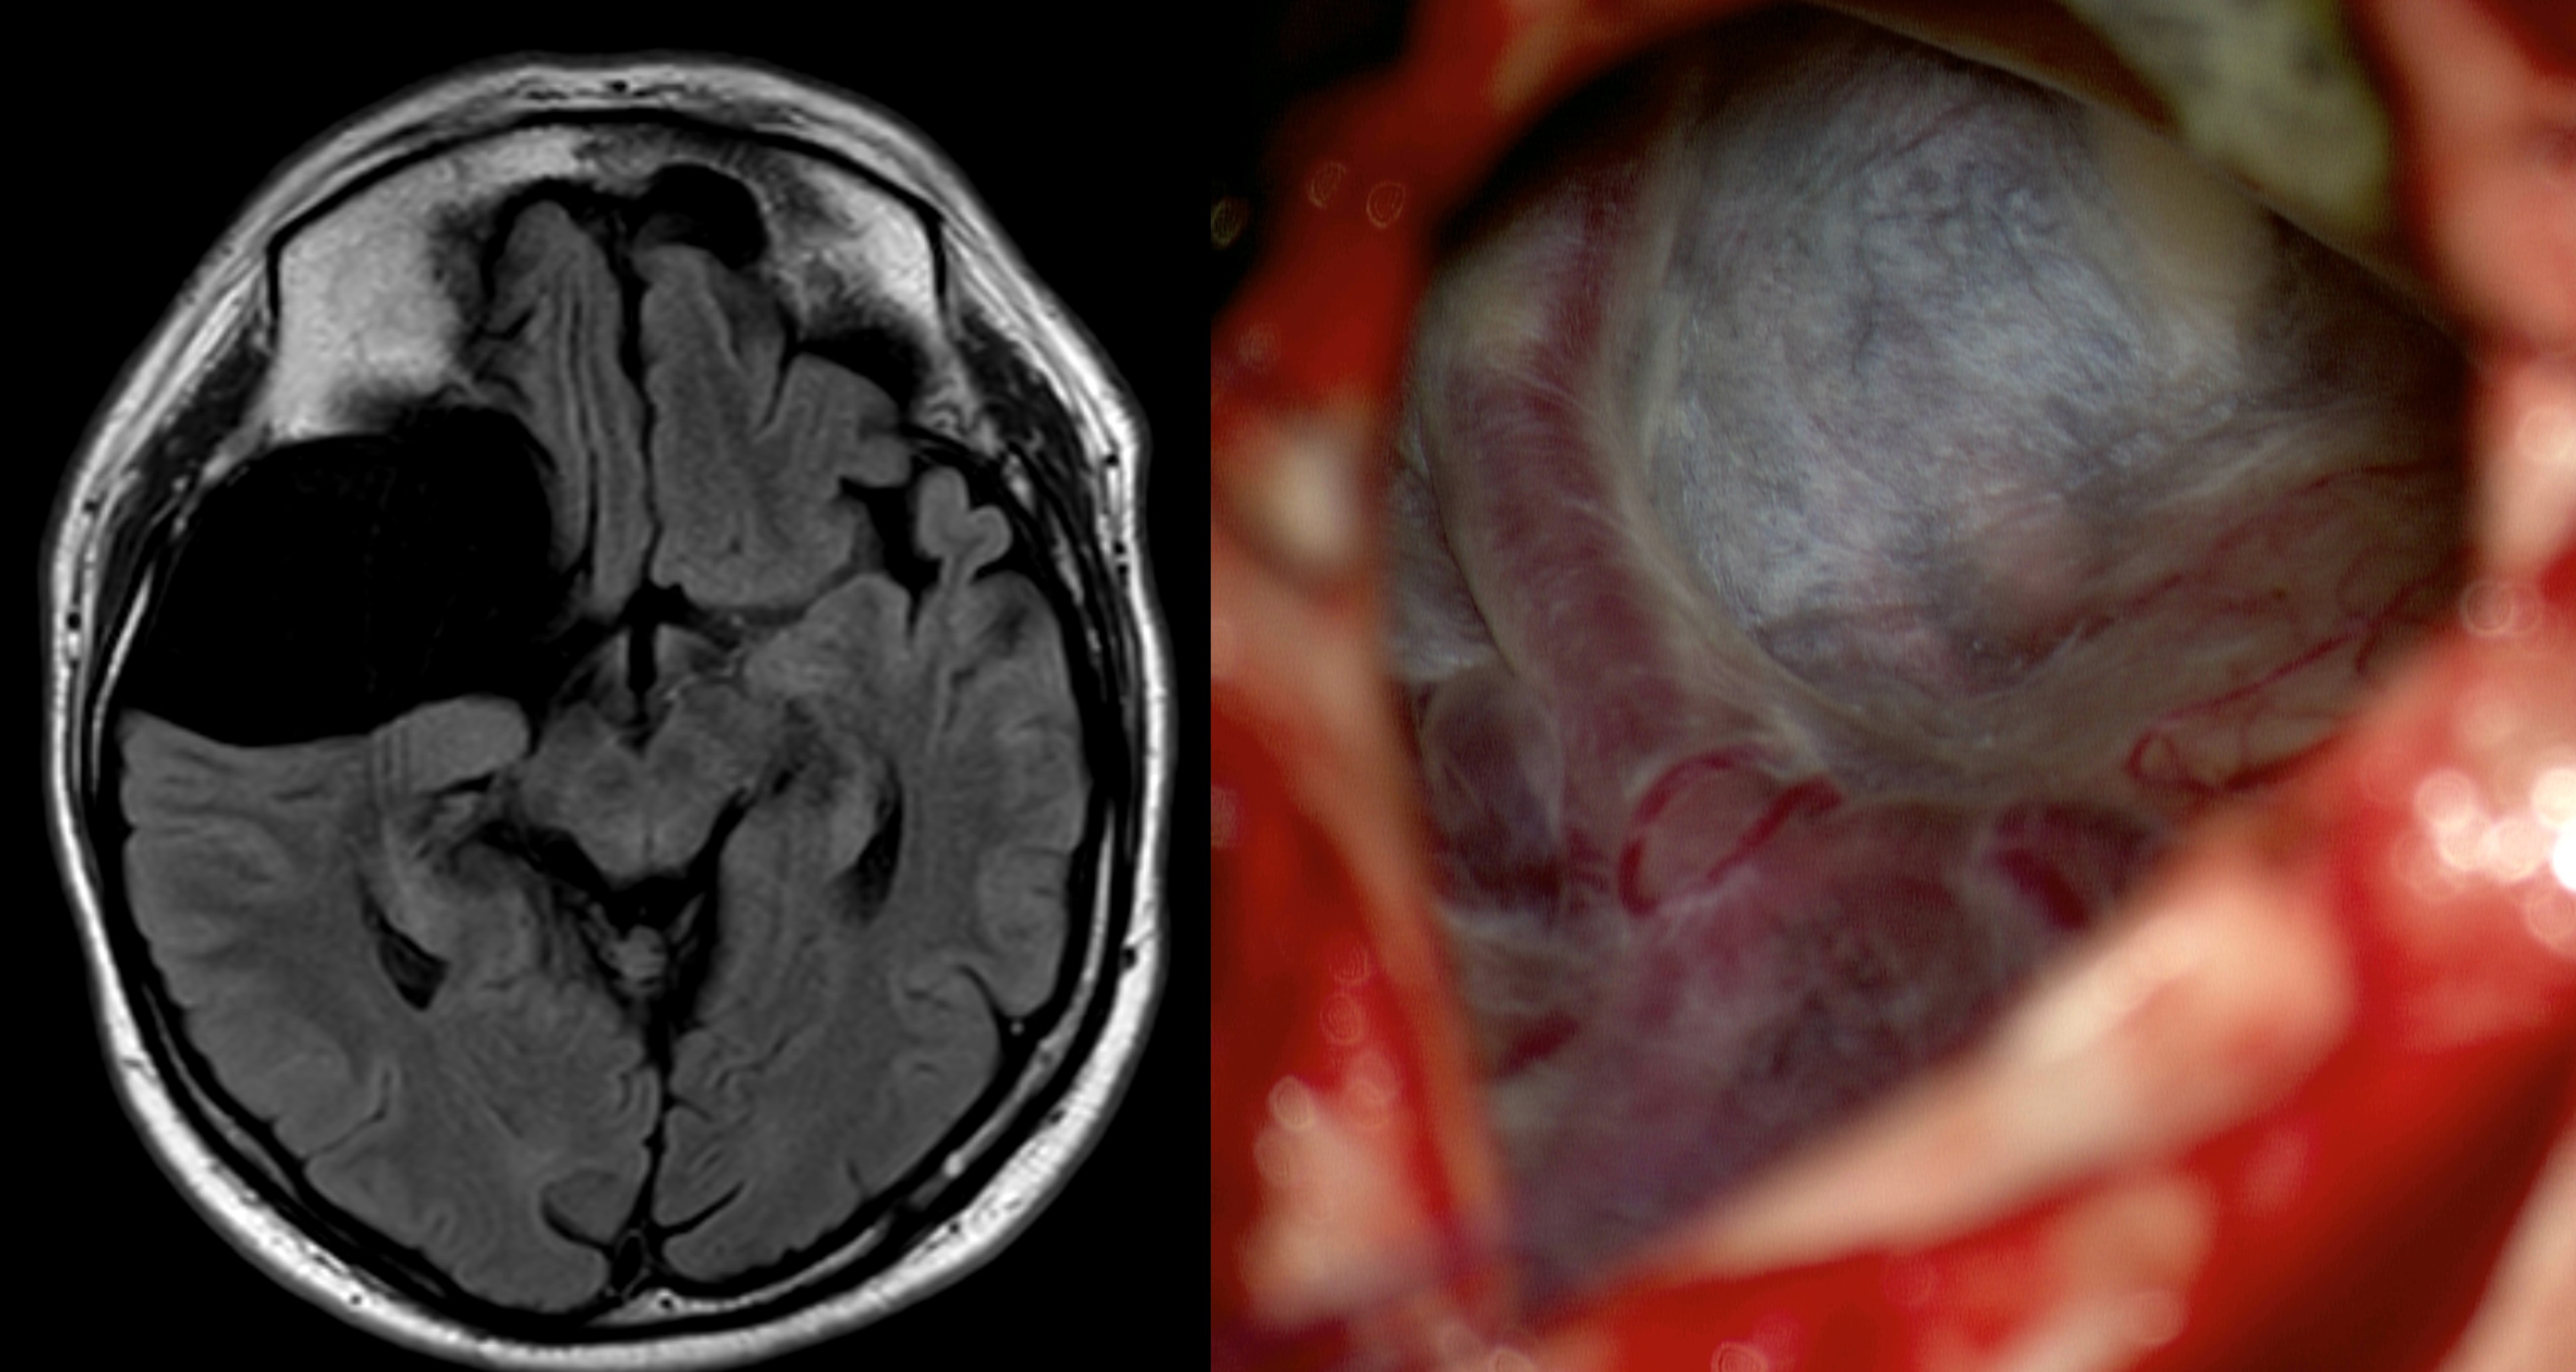

Intraoperativ

Arachnoidalzyste intraoperativ

Intraoperative Darstellung einer Arachnoidalzyste kurz vor deren Fensterung (rechtes Bild) mit dem zugehörigen MRT Bild (T1 Sequenz) im linken Bild.